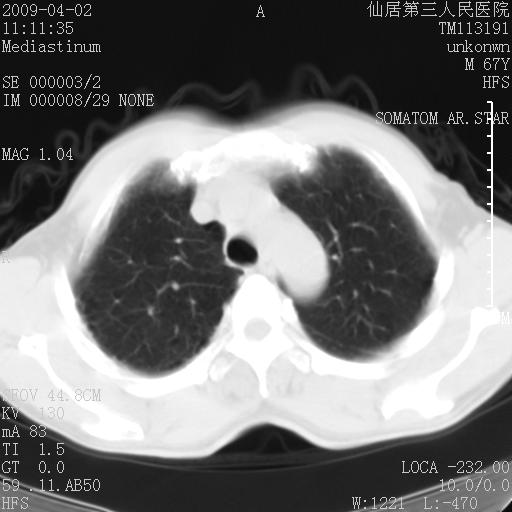

患者老年男性,乏力畏寒来诊,摄胸片示右下肺感染性病变,抗炎两周后复查胸片,无好转有进展。

后做ct平扫表现如下:

考虑右肺炎症可能性大,不除外细支气管肺泡癌

是否还要考虑肺间质纤维化,建议hrct扫描。

考虑间质性肺炎。

考虑双肺间质性改变(间质纤维化?)伴右肺下叶感染。

考虑间质性肺炎可能性大,患者卧床吗?坠积性肺炎代排

支持11楼,考虑肺结核.年䶨;大,抗炎无效.纵隔淋巴结肿大.老年人下肺结核要警提